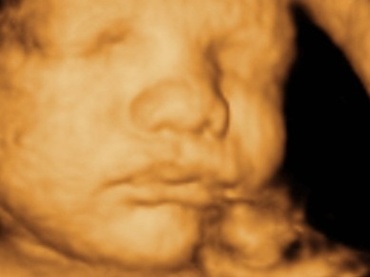

Oficial esti la finele celei de a VIII-a luni de sarcina, iar pana la momentul nasterii nu mai sunt decat, cel mult, sapte saptamani.

Doar patru la suta dintre femei nasc la termen. Marea majoritate a femeilor naste normal, undeva in intervalul cuprins intre a 38-a si a 39 saptamana a sarcinii. Este...